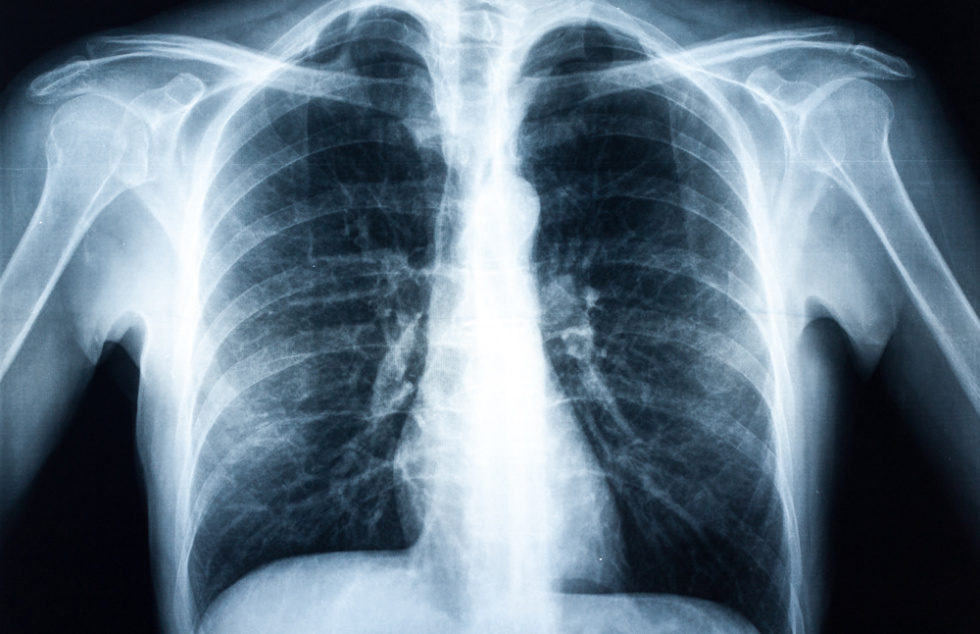

En concreto KeyZell han desarrollado un sistema de Inteligencia Artificial para el diagnóstico de cáncer por imagen. Se trata de una herramienta innovadora que permite mejorar la precisión del diagnóstico de cáncer por imagen a través de una radiografía o una tomografía por emisiones de positrones conocido como PET y las normas DICOM. El dispositivo ha sido entrenado con un total de 108.948 imágenes de rayos x de tórax correspondientes a 32.717 pacientes. El tiempo de procesado por radiografía es inferior a 1 minuto y permite la generación de colas de trabajo de manera simultánea por múltiples usuarios.

Esta herramienta de Medicina de Precisión es capaz ya de facilitar a los radiólogos detectar si un paciente posee masa tumoral con una precisión del 92% y ofrecer el diagnostico al radiólogo en menos de 1 minuto. El prototipo ha sido entrenado para cáncer de pulmón y cáncer de mama. Además ha sido validado por un comité ético